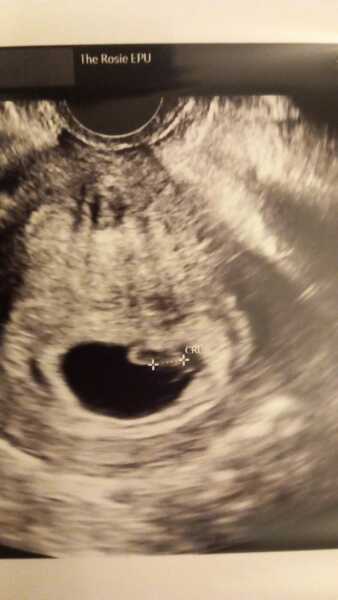

Hi Ladies glad your doing well @RW269 @Noisinmaro I have had 2 scans 1 @ 5 weeks and they couldn't find anything at all no sac went back week later and I had a sac with a faint.shadow thay looked like.start of something. Then went back again Friday just gone @ 7 plus 4 and I have a baby with a heartbeat. However they are suggesting I'm a week behind my dates amd measuring 6 plus 4 due to a 30 day cycle amd.laywr ovulation. Booked me for another scan with the miscarraige specialist lady on 20th Feb so I should be 9 weeks then as will showered but at this stage its a viable.pregnacy. can't believe it forst time i have seen a heartbeat as was no heartbeat on scans with previous pregnancies thay ended in MC. Still early days but its very possative news. .

@Racket81 this is such beautiful news!! Can’t wait to hear back on the 20th! It’s so so emotional seeing that little heartbeat flickering isn’t it! Got everything crossed for a positive scan for you! That’s the same day as my 12 week scan haha!